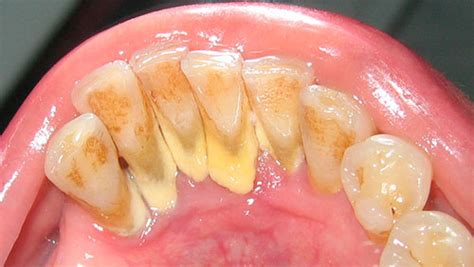

El sarro, también conocido como piedra dental, es la calcificación de la placa dental. La placa se origina a través del contacto entre la saliva y las bacterias derivadas de los alimentos. El sarro se identifica fácilmente como una pasta amarillenta o marrón que se adhiere a nuestros dientes.

La placa dental es una película blanquecina que se va depositando en la superficie dental, pero también en las encías. En un inicio, cuando la placa está blanda y no se ha solidificado formando el sarro dental o cálculo, el biofilm no es visible a simple vista. Si no eliminamos regularmente la placa inicialmente blanda cepillándonos los dientes, minerales como el calcio y el fosfato de la saliva se depositan en la biopelícula que se forma en los dientes. Esto provoca la calcificación de la placa y la formación de sarro duro.

- Sarro supragingival: Se produce por encima de la línea de las encías, preferentemente en la cara interna de los dientes frontales inferiores y en la cara externa de los molares superiores.